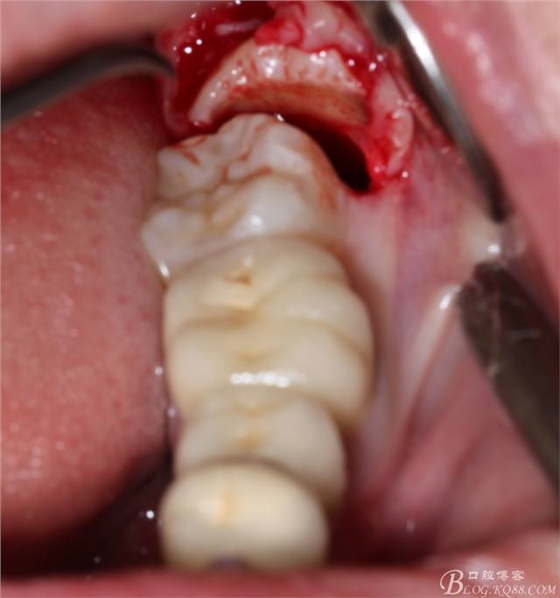

補(bǔ)完牙后,準(zhǔn)備撥除阻生智齒了。

先分析智齒的情況,口內(nèi)直觀是半個(gè)牙尖都沒露出來,差一點(diǎn)就完全埋伏了。磨牙后墊的可操作面積中規(guī)中紀(jì),X全景片示三類阻生,根冠比例是1:1,非融合根,近中根壓下頜管。

640 (6).jpg